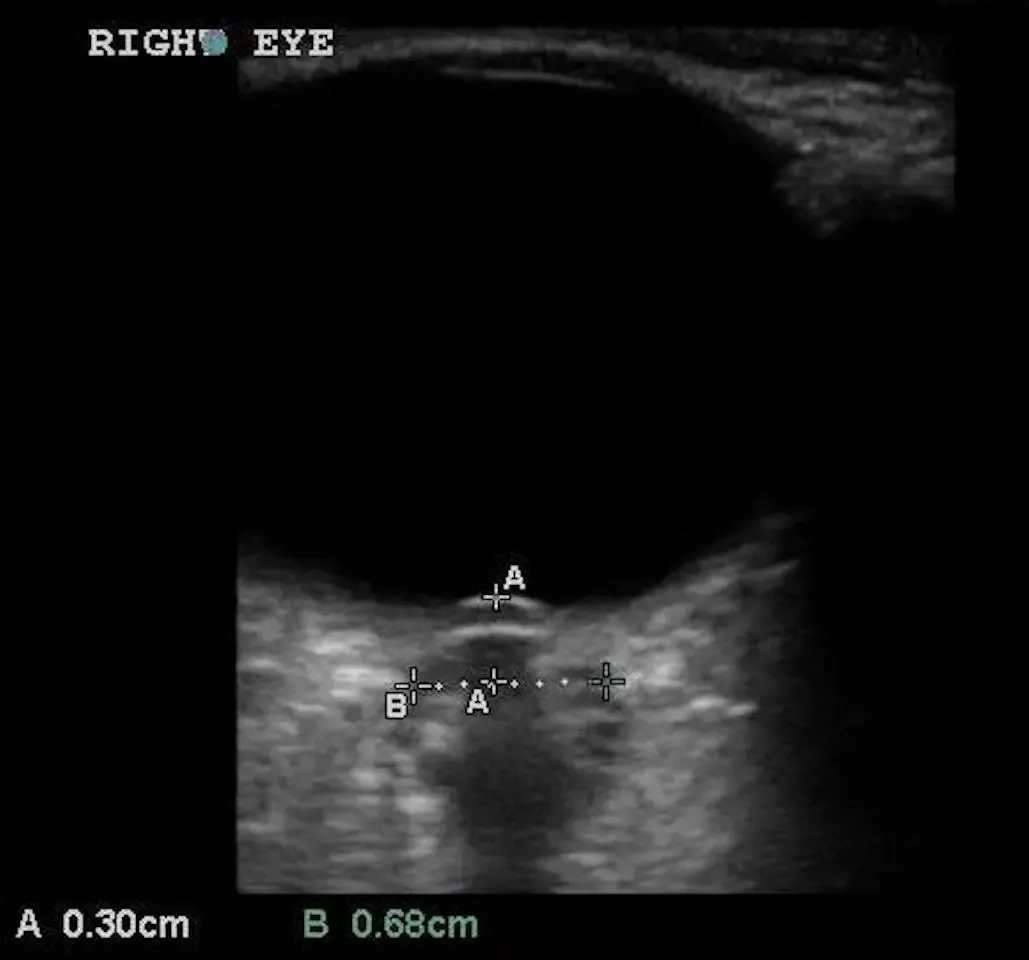

ONSD를 측정하기 위해서는 3×5를 기억해야 한다.

양쪽 눈에서 Globe의 posterior aspect에서 3mm 뒤쪽에서 측정한다

5 mm 미만은 정상, 5~6 mm 는 indeterminate, 6mm 초과는 증가한 것으로 판단

optic disc의 ant. peak 와 globe의 post. surface 사이 거리 > 0.6 mm

→ Papilledema